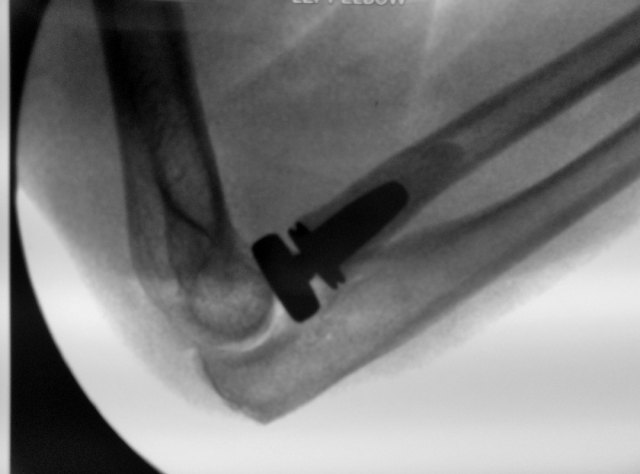

Radial Head Replacement

A radial head replacement can provide excellent results with early mobilization of the elbow.

This is a video showing the possible excellent results as early as 1 week post-surgery.